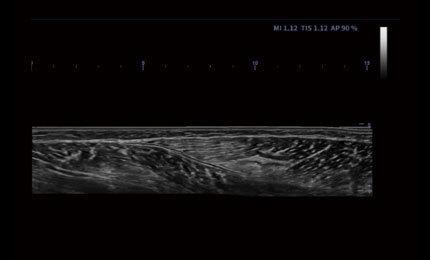

Auto IMT

Automatic identification and measurement of intima-media thickness. Both left and right blood vessels, anterior and posterior walls can be measured.